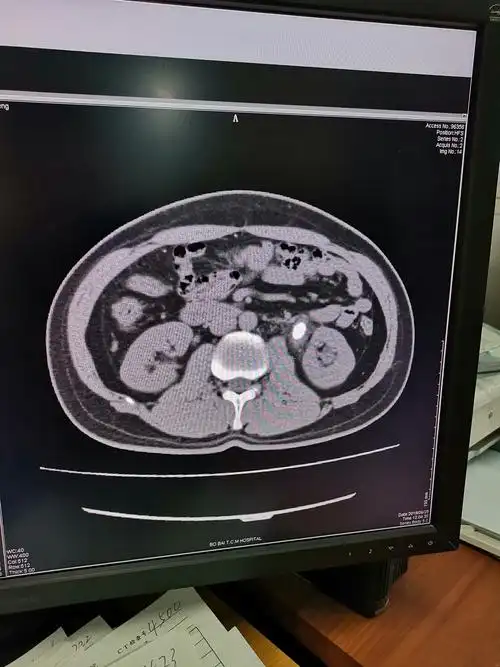

震波碎石后复查ct提示右侧肾盂输尿管连接部小结石,右输尿管中下段

右侧输尿管结石伴肾盂输尿管积水一例(男性,63岁)